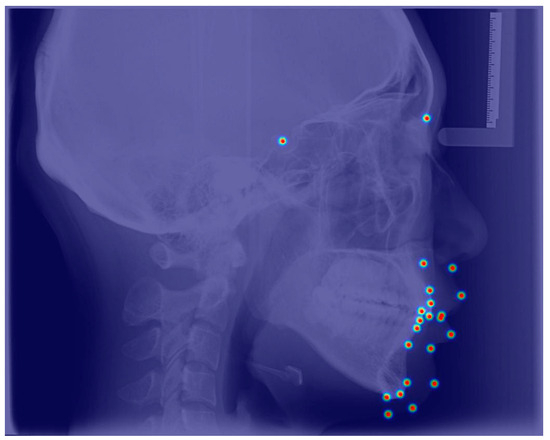

| No. | Landmarks |

|---|---|

| 1 | Sella (S) |

| 2 | Nasion (N) |

| 3 | Subspinale (A) |

| 4 | Superior prosthion (Spr) |

| 5 | The most labial surface of the upper incisor (UJ) |

| 6 | Upper incisor (UI) |

| 7 | Lower incisor (LI) |

| 8 | The most labial surface of the lower incisor (LJ) |

| 9 | Infradentale (Id) |

| 10 | Supramental (B) |

| 11 | Pogonion (Po) |

| 12 | Gnathion (Gn) |

| 13 | Menton (Me) |

| 14 | Subnasale (Sn) |

| 15 | Labrale superius (UT) |

| 16 | Stomion superius (UL) |

| 17 | Stomion superius (LL) |

| 18 | Labrale inferius (LT) |

| 19 | Inferior labial sulcus (Bs) |

| 20 | Pogonion of soft tissue (Pos) |

| 21 | Gnathion of soft tissue (Gns) |

| 22 | Menton of soft tissue (Mes) |

| 23 | Ruler point 1 |

| 24 | Ruler point 2 |